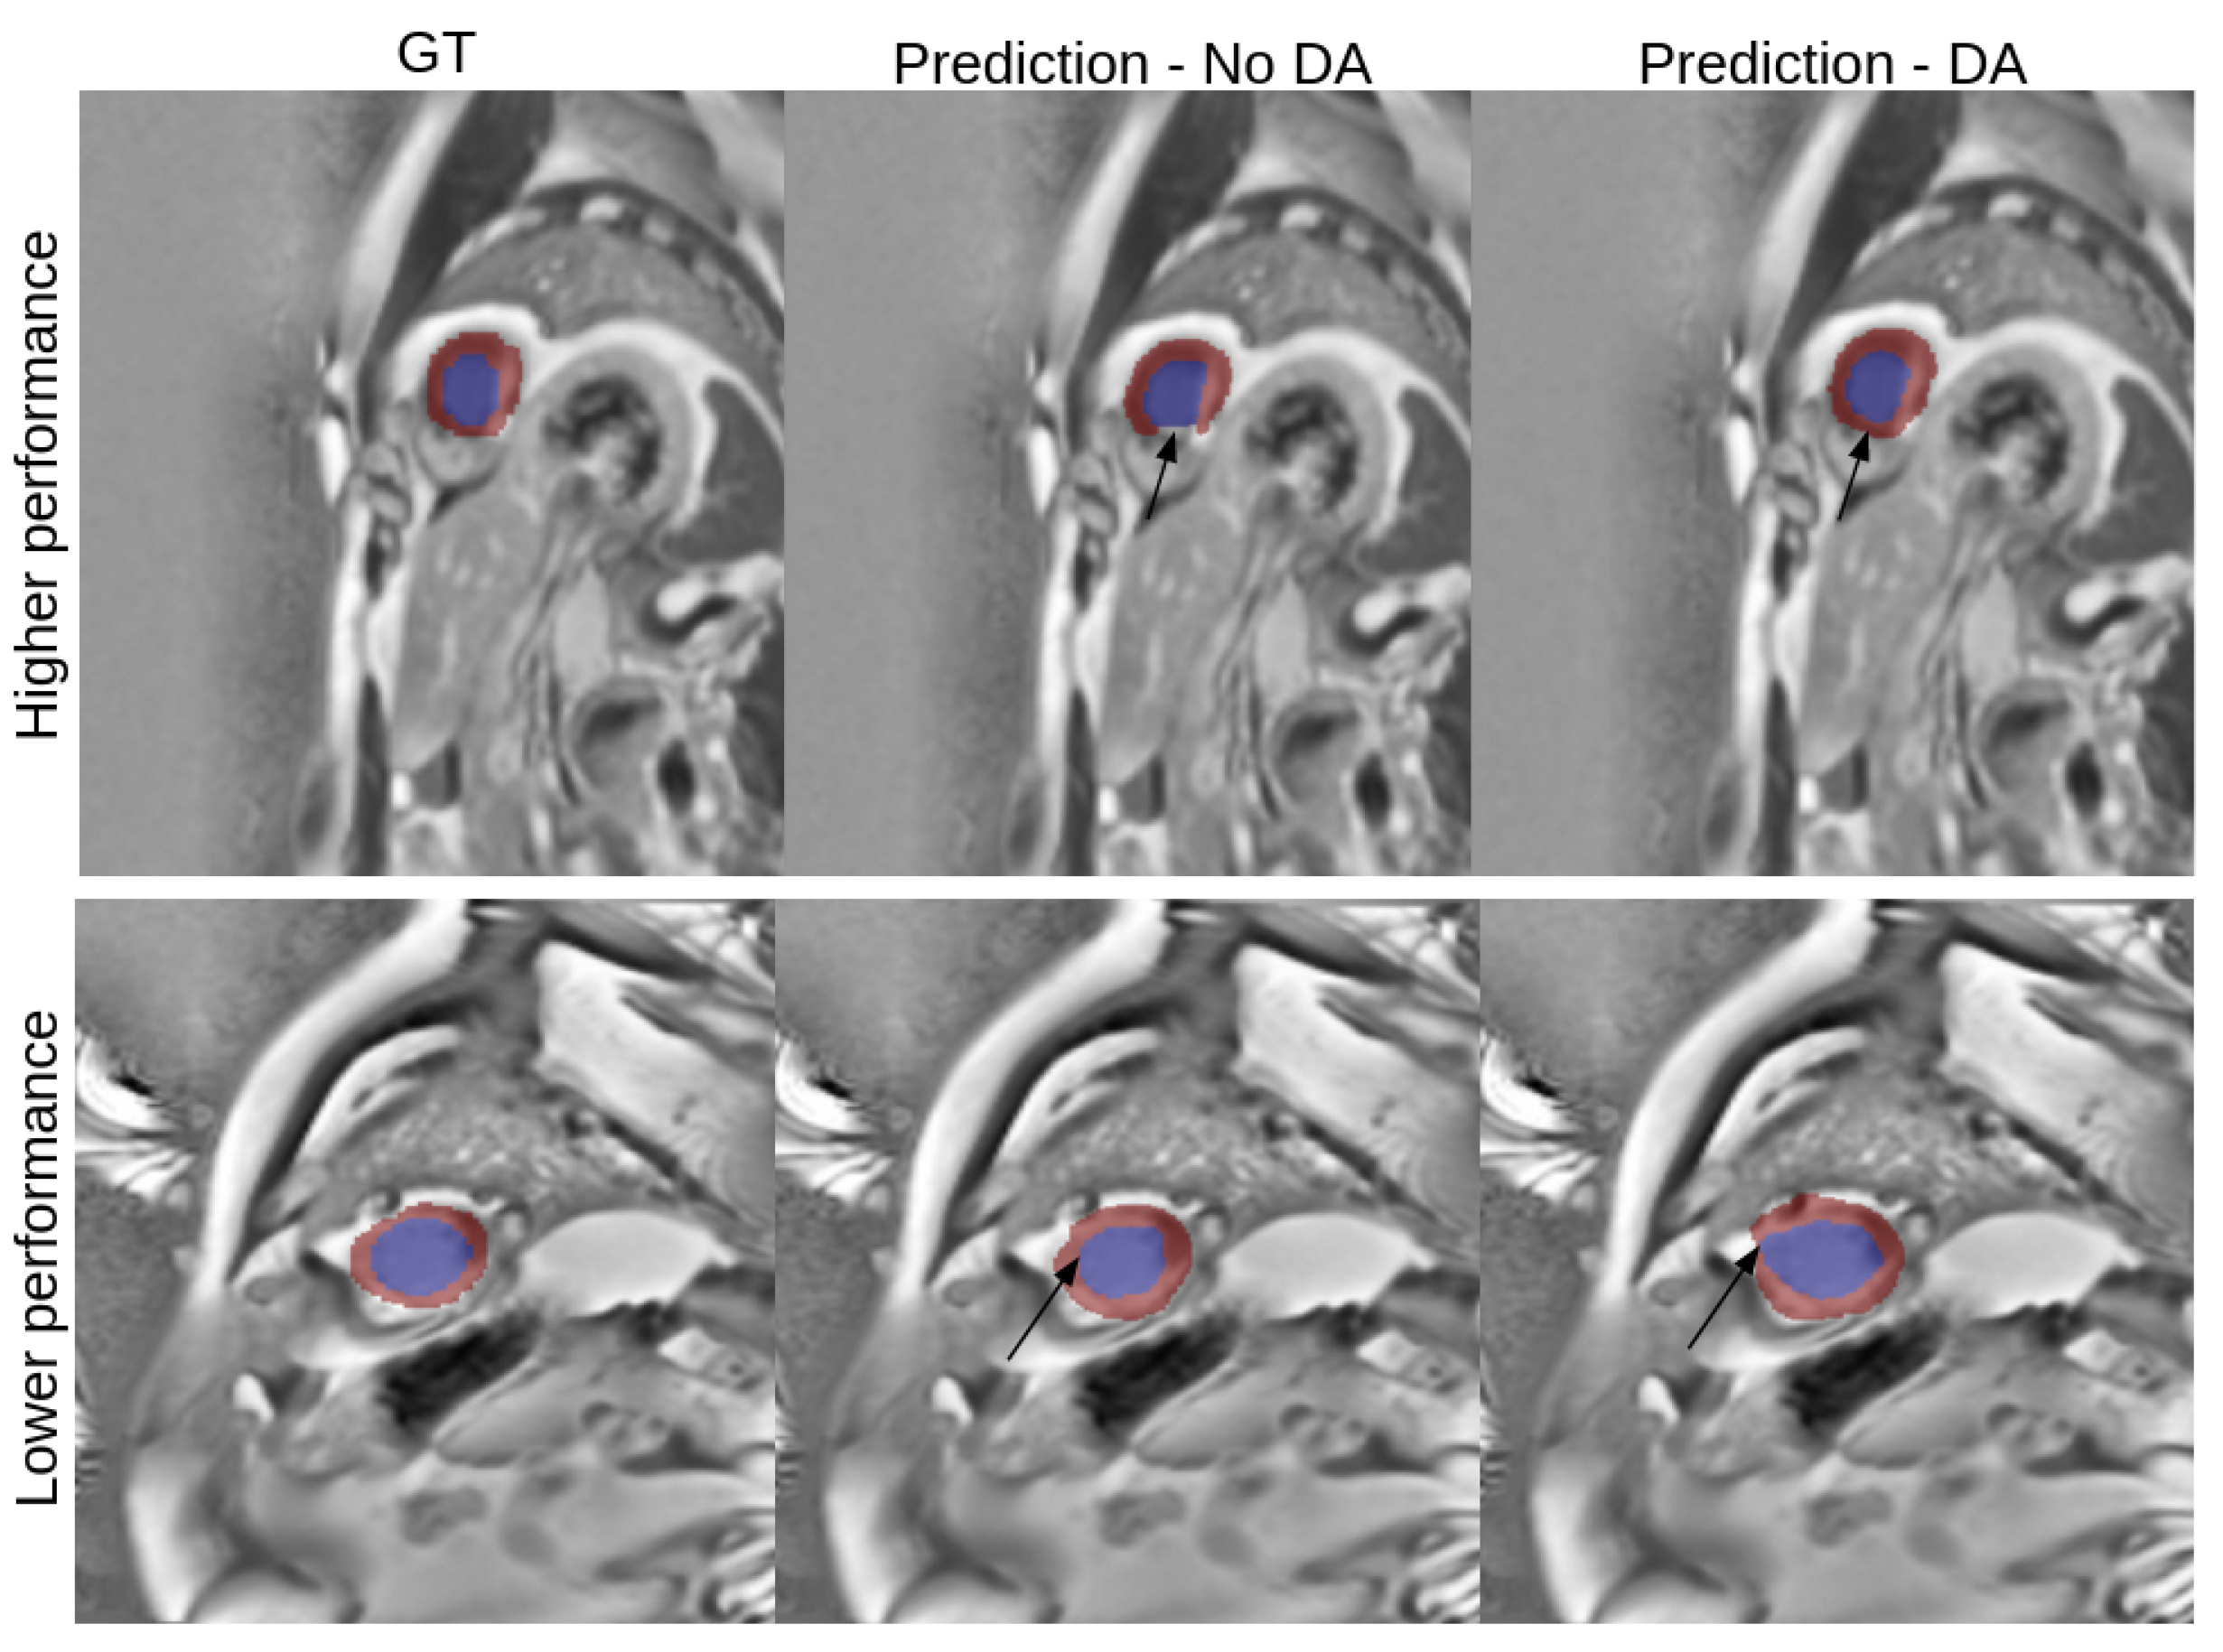

3.1. Single Modality

3.2. Multi Modality

3.4. Best Model Further Results